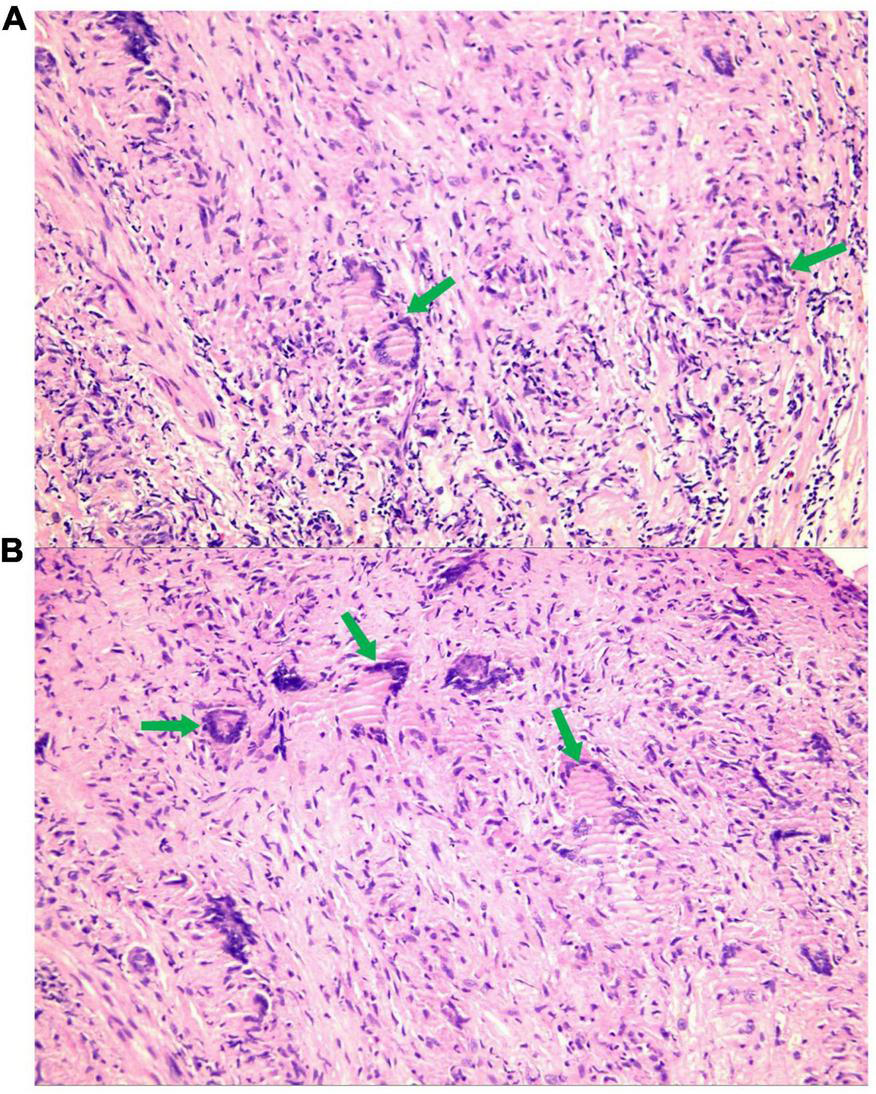

FIGURE 4

A large number of epithelioid nodules composed of epithelioid cells, multinucleated giant cells [A,B (green arrow)], and lymphocytes are found in the myocardium and endocardium.

To further clarify the cause of arrhythmia, we performed an EMB. To accurately locate the lesion and improve the success rate of the EMB, the patient underwent the last CMR (Figure 3). Using CMR imaging guidance, EMB was taken from interventricular septum tissue of the right ventricle. EMB revealed a large number of epithelioid nodules composed of epithelioid cells, multinucleated giant cells, and lymphocytes in the myocardium and endocardium. However, no necrotic tissue was found on acid-fast staining (–) (Figure 4). Based on the clinical manifestations, imaging data, and pathological features, we diagnosed the patient with ICS. Thereafter, the patient received dual-chamber implantable cardioverter defibrillator to prevent sudden death, while prednisone (35 mg/d) was administered to treat sarcoidosis. Additionally, spironolactone (20 mg/d) and daglitazine (10 mg/d) were administered to delay ventricular remodeling.